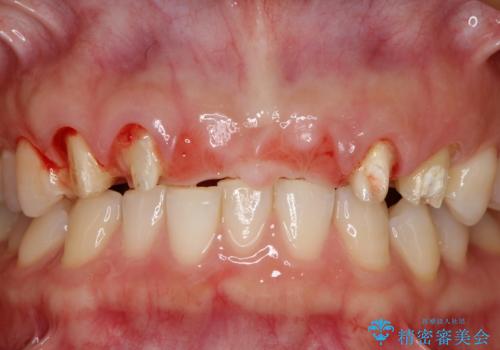

- 数ヶ月前に治療終了したブリッジの歯ぐきの違和感が強く、改善を求めて来院されました。

歯ぐきは著しく腫れ、少し触ると出血してしまうような状態であったためブリッジの再作製・歯周外科を用いた歯肉環境の改善を計画します。